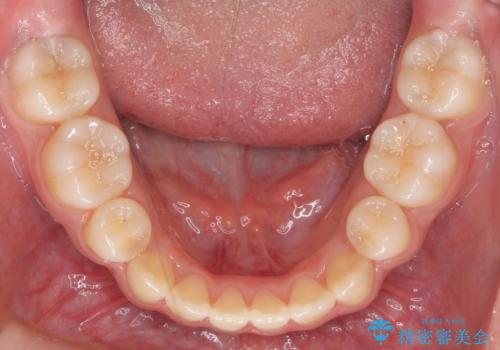

インビザラインチェンジで成功 インビザラインで八重歯の抜歯矯正

- かみ合わせを主訴に来院。

八重歯や、前歯のオープンバイト(開咬)の症状があり、マウスピース(インビザライン)矯正単独では治すのが難しい症状が複合していました。

八重歯や抜歯したスペースの閉鎖をワイヤー矯正で前半行い、治療後半は目立たないインビザラインでかみ合わせを調整しました。

ワイヤー矯正からインビザラインへの変更は、歯磨きも簡単になり、目立たず、さらにワイヤーと併用することで妥協せずしっかり治療結果も出すことができます。